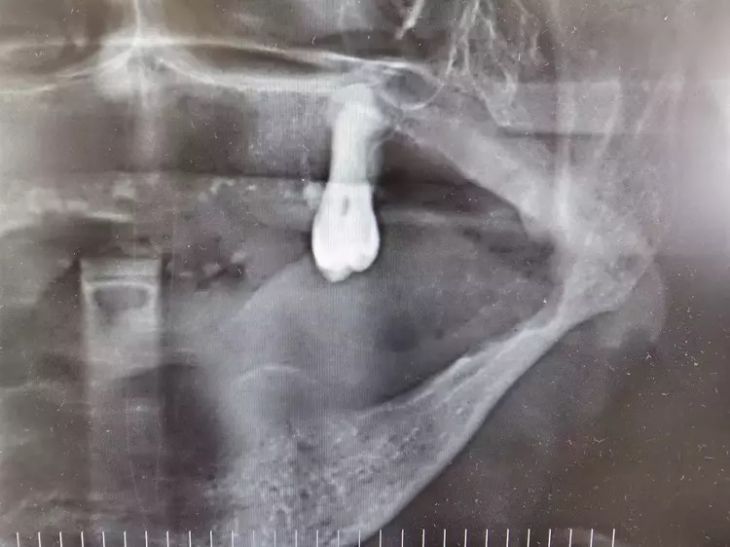

OMÜ Diş Hekimliği Fakültesi Dekanı Prof. Dr. Kaan Gündüz, vatandaşların ağız içi yaraları çoğu zaman önemsemediğini, tütün kullanımı, yetersiz ağız bakımı, güneş maruziyeti ve HPV virüsünün ağız kanserlerinin artışında etkili olduğunu ifade etti. Ağızda 2 haftadan uzun süren yaralar, sebepsiz diş sallanması, uyuşukluk ve çene ağrıları mutlaka dikkate alınması gerektiğini belirten Prof. Dr. Gündüz, ağız kanserinden korunma yolları arasında tütün ve alkol kullanımını azaltmak olduğunu belirtti. Prof. Dr. Gündüz, “Oral kanserler dediğimiz şey aslında başlangıçları çok hızlı ve sinsi gelişen durumlar. Bundan dolayı mutlaka hastaların 2 haftadan uzun süren ağızdaki yaraları eğer mevcutsa en yakın diş hekimlerine başvurmaları gerekmekte. En son yapılan, 2022 yılında Sağlık Bakanlığı yapmış oldu araştırmada 2 bin 246 tane ağız kanserine rastlanmış. Bu vakaların 551 tanesi ölümle sonuçlanmış. Bu da Türkiye kanser görülme olasılığını yüzde 1'ine tekabül ediyor ama şimdi şöyle bir durum var. Şimdi bizim insanlarımız kulağından bir damla kan gelince hemen işte gerekli doktora gider iken ağzından kan gelme durumunda çok fazla önemsemiyor. Yani ağız, dişler çok fazla önemsemiyor ne yazık ki. Ancak Özellikle son yıllarda artan tütün kullanımı ki bunun formasyonları var biliyorsunuz işte ne bileyim nargilesinden, piposundan, purosundan artmasından dolayı oral hijyenin, ağız bakımının eksikliğinden dolayı ve son yıllarda özellikle sizlerin de televizyonlarda veya işte bazı haber kanallarına duyduğunuz Human Papilloma Virüsü dediğimiz HPV'nin yaygınlaşmasından dolayı güneşe maruziyetinden dolayı insanlarda özellikle oral kanserler çok daha fazla sıklıkla görülüyor” diye konuştu.

Ağız kanserinde erken tanı gerçekleşirse hastaların ölümle sonuçlanmasının önüne geçilebileceğini ifade eden Prof. Dr. Gündüz, “Biz kurum olarak Karadeniz'in en büyük üniversitesiyiz ve de fakülte olarak da Karadeniz'de büyük bir hizmet vermekteyiz. Ortalama yaklaşık günde 500 hasta, aylıkta 10 bine yakın hasta bakıyoruz. Biz yapmış olduğumuz seminerlerde hem öğrencilerimizi hem asistanlarımızı hem de halkımızı bu konuda bilgilendirmeye çalışıyoruz. Erken tanı eğer gerçekleşirse bu hastalıkların ölümle sonuçlanmasının nispeten önüne geçmiş oluyoruz. Çünkü erken tanı biliyorsunuz her kanser vakasında çok önemli bir yer tutmakta. Herhangi birisi ağzında eğer 2 haftanın üzerine geçmeyen bir yara varsa mutlaka en yakın diş hekimine başvurması gerekmekte. Sebepsiz yere dişlerin sallanması, uyuşukluk olması, yüzde sebepsiz ağrıların, çene bölgesinde sebepsiz ağrıların oluşması kanserlerin başlangıç bulguları arasındadır. Zaten kanserlerin en fazla oluştuğu yerler ağız içerisinde dilin özellikle arka kenarlarıdır. Bunlar ne yazık ki başlangıçları da ağrısız olduğu için bir kısmının gözden kaçabilmekte. O yüzden insanlarımızdan, halkımızdan bu konuda dikkat etmeleri, eğer böyle bir lezyonla muhatap olurlarsa mesela bir yakınından ağız içerisindeki görüntüsünü çekmesini talep etmeli. 2 hafta sonra da aynı şekilde bu görüntü duruyorsa veya daha da büyümüşse en yakın merkeze gitmesini önermekteyiz” ifadelerini kullandı.